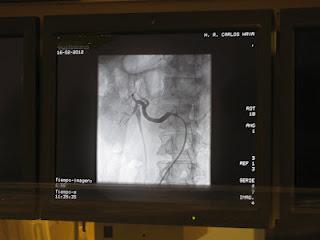

La técnica, utilizada por primera vez en Andalucía, consiste en reducir esa actividad nerviosa del interior de la pared de las arterias renales a través de un catéter, que introducido a través de la arteria femoral y alojado en dichas arterias, recibe impulsos eléctricos en espiral desde un generador externo, produciendo la ablación, o ‘denervación’, de los nervios simpáticos renales.

El tratamiento se realiza en la sala de radiología vascular intervencionista, con el paciente bajo sedación, la duración es de unos 45 minutos, aproximadamente, y una vez finalizado el tratamiento, se retira el catéter.